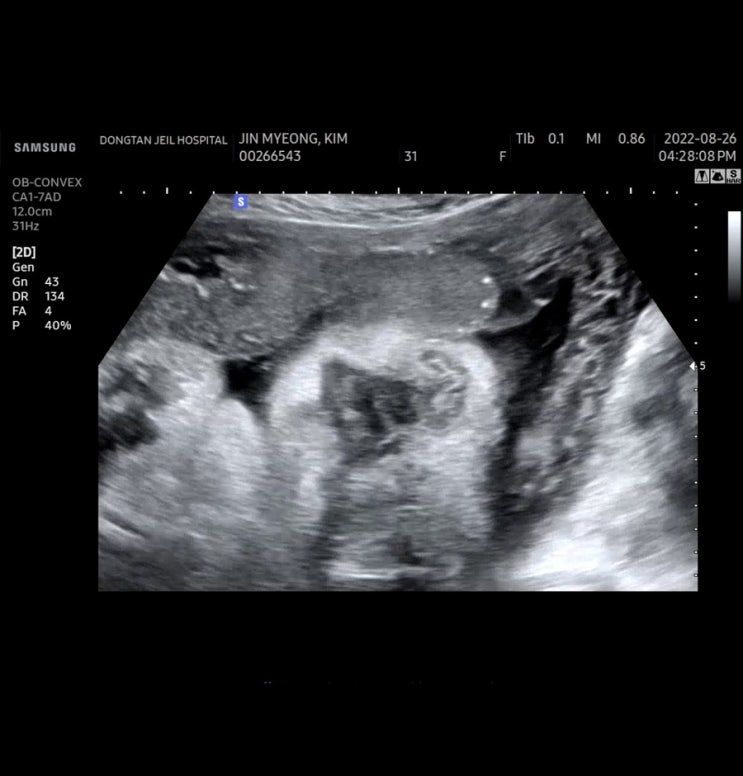

37주 6일차 동탄제일병원 검진 (초음파)

9월 10일 예정일인 호떡이 벌써 37주 6일차가 되었다 오후 4시 20분 검진예약 소변스틱 검사 하구 초기 검...